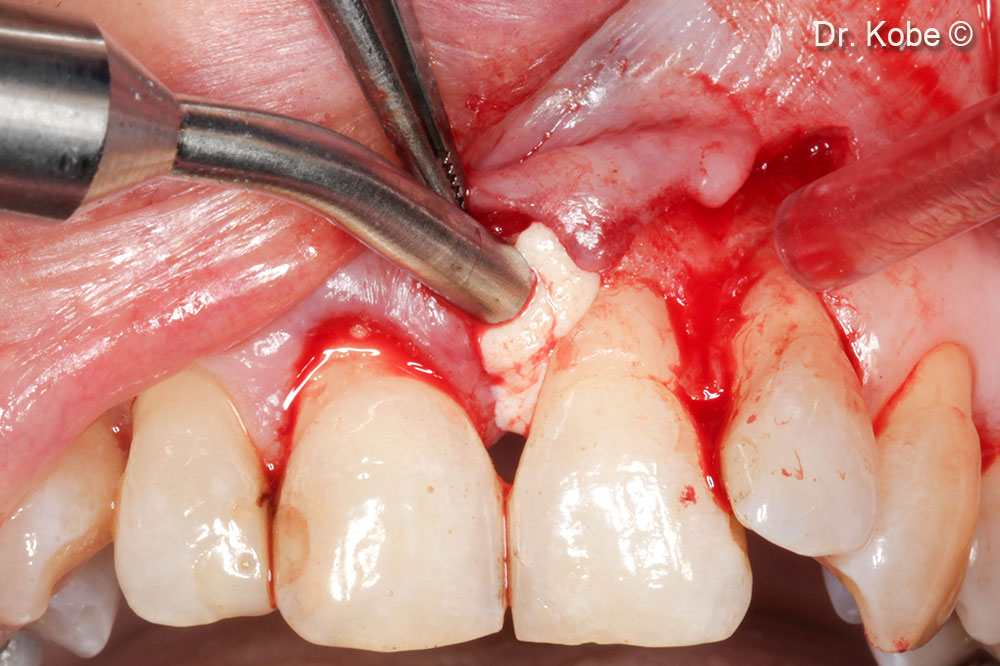

4. Access to the defect

5. Root scaling and debridement